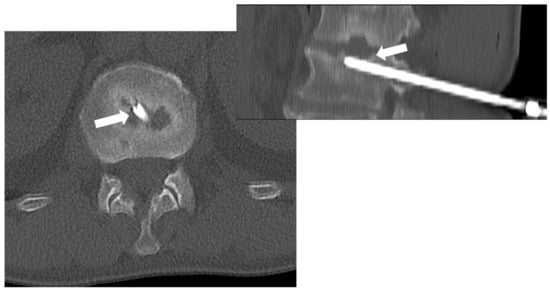

Figure 8. CT-guided biopsy in a 55-year-old male with suspected spondylodiscitis; CT (axial view on the left—sagittal reconstruction on the right) permits to guide the tip of the needle (8 gauge) into the end plate erosion (arrows) adjacent to the disc.

Among the imaging tools that can guide the biopsy procedure, CT is the most used and effective, particularly in reaching the spine safely. Indeed, CT guidance is superior to fluoroscopic guidance, especially for small spinal lesions. Most importantly, it can guide procedures in all skeletal areas (including spinal segments) (Figure 8) [67].